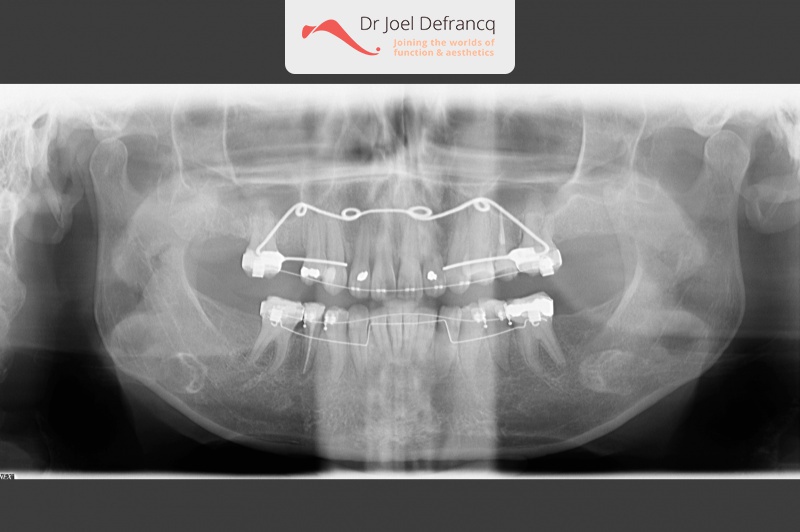

Paola: Diepe beet, overbeet

Kaakchirurgie

- Verlenging onderkaak (BSSO)

- Kinchirurgie

- Onderrand shaving der onderkaak